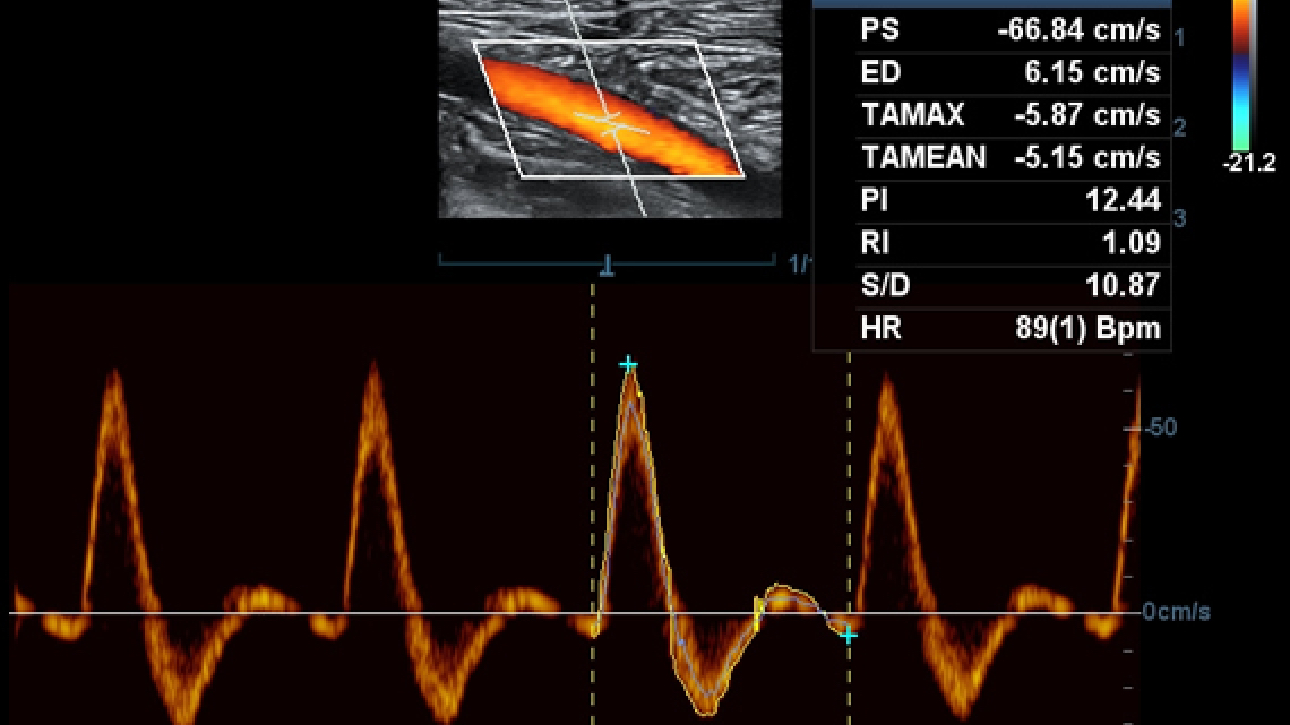

Smart Track

ItŌĆÖs Mindray unique feature to reduce repetitive, time-consuming scanning steps in vascular exams. Smart Track provides intelligent and real-time vessel tracking and real-time image optimization of Color and PW.